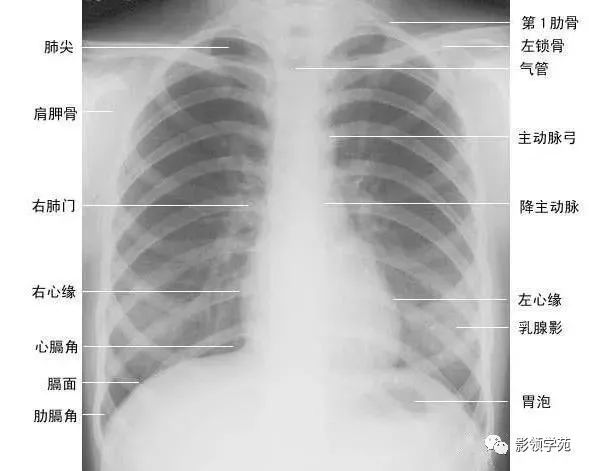

两肺含有空气,因而可与周围组织及器官形成鲜明的自然对比,胸部x线平片为诊断提供了极为有利的条件。由于胸部x线影像是胸腔内、外各种组织和器官重叠的复合影像,同时常常存在解剖变异等因素,因此掌握正常x线解剖是识别和分析胸部病变的基础。

正常胸廓由软组织与骨骼组成,两侧对称(如下图)。

(一)软组织

1、胸锁乳突肌及锁骨上皮肤皱褶 胸锁乳突肌起自胸骨柄及锁骨内端,向后上方斜行,止于乳突,在两肺尖内侧形成外缘锐利且较均匀的致密阴影。在胸骨头和锁骨头及锁骨之间形成一个小三角间隙,叫锁骨上窝或胸锁乳突肌间隙。当颈部偏斜时,两侧胸锁乳乳突肌阴影可不对称,勿误为肺尖部病变。锁骨上皮肤皱褶为与锁骨上缘平行的薄层软组织影,其厚度为3~5mm,内侧与胸锁乳突肌阴影相连,略成直角,系锁骨上皮肤及皮下组织的投影。

2、胸大肌起于锁骨的外侧分,胸骨和第1~6肋软骨,肌束行向外上方,至于肱骨大结节嵴。在肌肉发达的男性,于两肺中部的外侧形成扇形均匀致密影,下缘锐利呈斜行曲线,自肺野伸向腋部,与腋前皮肤皱褶相延续。

3、乳房及乳头 女性乳房于两下肺野形成半圆形的密度增高影,其下缘清楚,并向外与腋部皮肤连续,上缘不清,且密度自下而上逐渐变淡以至消失,其位置随年龄的增长而下垂,一般两侧对称。乳头在两下肺野相当于第5前肋间处形成边缘清楚的小圆形致密阴影,乳房越薄,乳头影境界越清晰,其特点亦为左右对称。青春期乳头呈半球状,约在第2~6肋之间。妊娠期乳腺可明显增大,至哺乳期结束后,乳房逐渐缩小,失去弹性而下垂,到老年期,乳房逐渐萎缩。

(二)骨骼 胸廓前有胸骨、锁骨,后有胸椎、肩胛骨,肋骨则围绕其间。